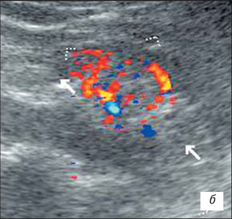

УЗІ нирки при запальних змінах в режимі ЦДК

а – інтраренальний судинний малюнок нирки збережений, кортикальный кровотік визначається у всіх відділах паренхіми;

б – збіднення судинного малюнка;

в – швидкісні показники в гирлі ниркової артерії в межах вікової норми: Vps – 83,7 см/с; Ved – 34,1 см/с; RI – 0,63; PI – 0,96.

На розгорненій картині УЗІ з ЦДК характеризується нерівністю, нечіткістю, деформацією контура нирки, який місцями може не простежуватися; нирка іноді місцями погано диференціюється від навколишніх тканин, що утрудняє визначення її розмірів; візуалізуються дрібні, неправильної форми втягнення контура, розподілені або по всьому контуру, або в якомусь фрагменті нирки; визначається нечіткість кортико-медуллярной диференціювання; є виражені дифузні зміни паренхіми нирки з помірним нерівномірним підвищенням її эхогенності; дилатація чашечно-мискової системи; фрагментарне стоншування паренхіми нирки з компенсаторним потовщенням або збереженням товщини інших її ділянок помірне збіднення інтраренального судинного малюнка, найбільш виражене в місцях деформації і втягнення контура нирки; зниження швидкісних характеристик артеріального кровотоку (мал. 3).